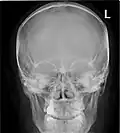

![]() Paranasal sinuses seen in a frontal view | |

Paranasal sinuses radiograph (occipitofrontal) -